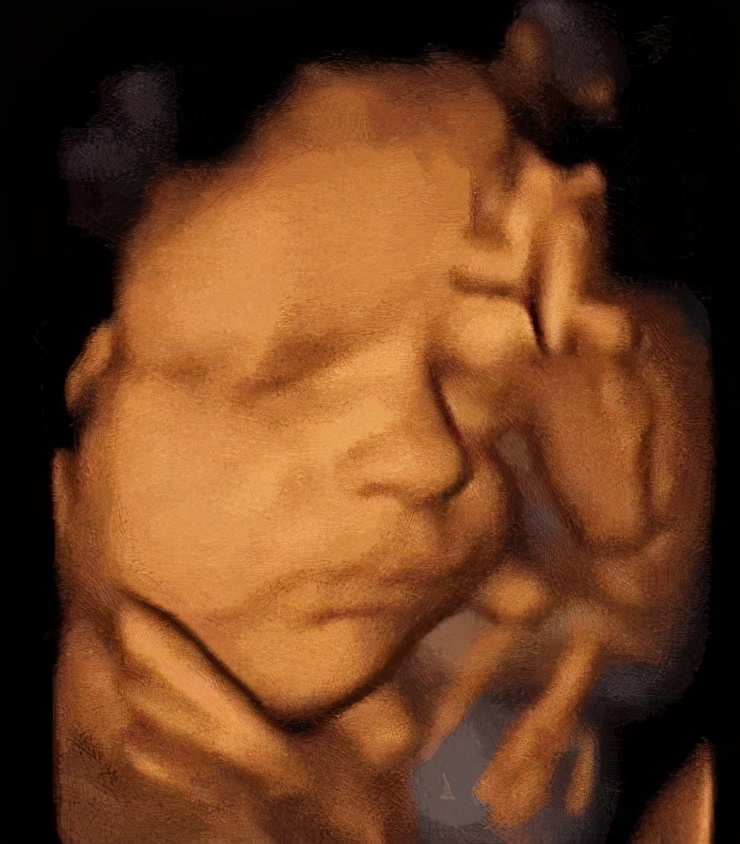

三维图像是这样的

四维彩超动图是这样的